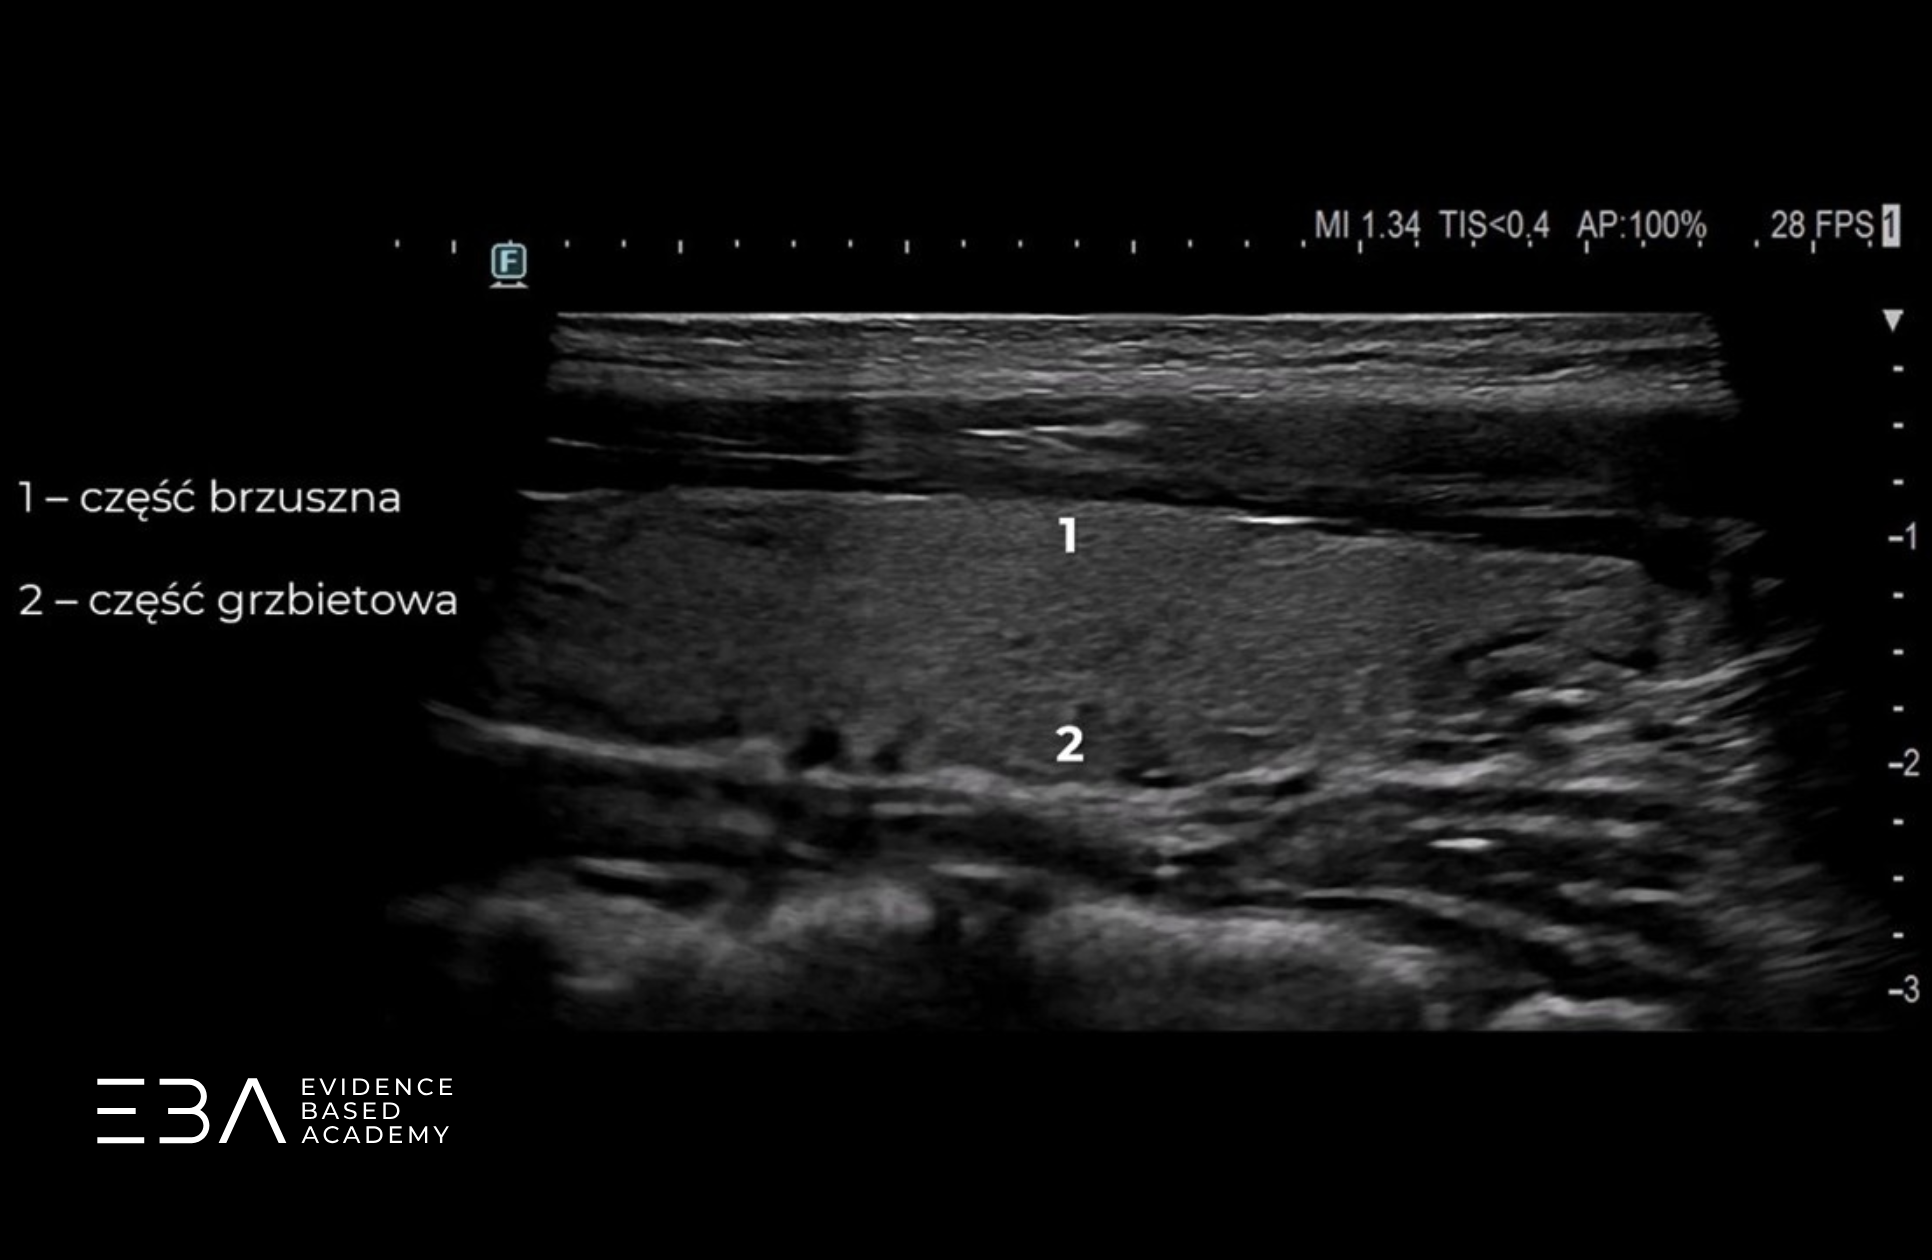

W projekcji podłużnej możemy podzielić płat na trzy części. Po lewej stronie obrazu (po stronie znacznika) widoczna jest część górna (inaczej biegun górny), na środku – część środkowa, a po prawej stronie obrazu – część dolna (inaczej biegun dolny).

Projekcja podłużna z podpisami części płata.

W projekcji podłużnej możemy również wyodrębnić część przednią, bliższą czoła głowicy (część brzuszną) oraz część tylną (grzbietową). Podział tarczycy na poszczególne części jest orientacyjny i służy głównie do opisu lokalizacji zmian ogniskowych widocznych wewnątrz tarczycy lub w jej okolicy.

Projekcja podłużna z podpisami zarysu przedniego i tylnego.